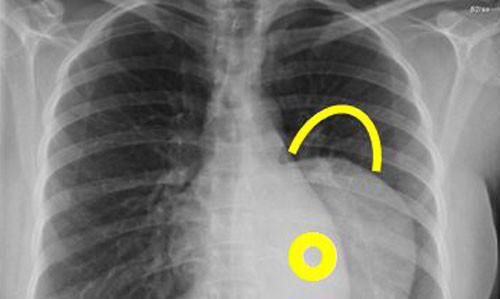

Hình ảnh một khối u trung thất.

Các bác sĩ đã phẫu thuật cưa mở toàn bộ xương ức, mở rộng lồng ngực để tiến hành cuộc mổ. Khối u rất lớn, mật độ chắc, phát triển lan tỏa ra xung quanh vào khoang màng phổi 2 bên, chèn ép đẩy lệch khí quản, tim , phổi và mạch máu, u bọc quanh các dây thần kinh.